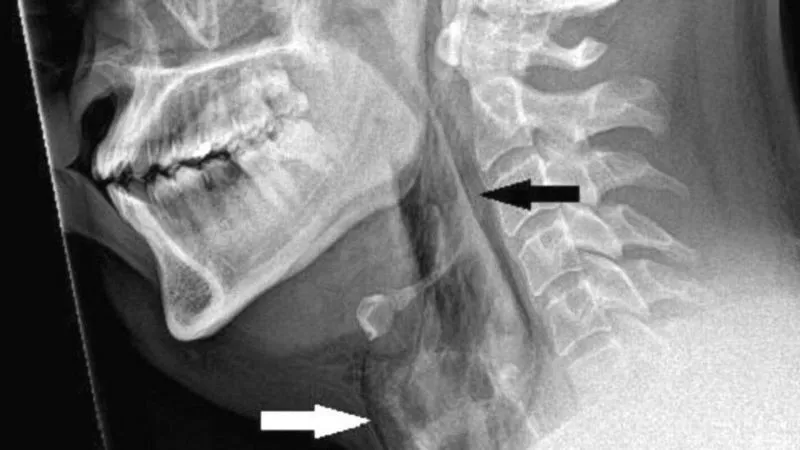

Una radiografía confirmó que se filtraba aire de su tráquea hacia los tejidos blandos del cuello y de la espalda a través de una fisura.